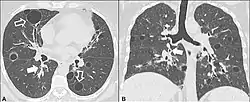

| CT scan of lymphocytic interstitial pneumonia, with pulmonary cysts. | |